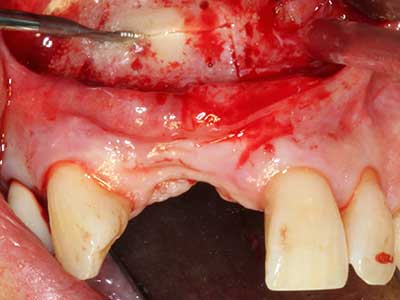

El tejido óseo no solo tiene un contenido puramente mineral, sino que también presenta una importante proporción de fibras de colágeno. Esto no solo garantiza una buena resistencia a la presión, sino también una cierta flexibilidad, que puede aprovecharse para la realización de aumentos. En la plastia de expansión clásica a efectos de una partición ósea, la cresta maxilar atrofiada se divide en su eje longitudinal y, tras alcanzar una profundidad de osteotomía suficiente, se extiende con cuidado (fig. 13-16), en un caso ideal sin desperiostizar de forma visible el maxilar (Brugnami, Caiazzo et al. 2014, Stricker, Fleiner et al. 2014). Los sistemas de tornillos y placas con distancia de expansión creciente han demostrado su eficacia para distanciar entre sí las dos tablas óseas por debajo del umbral de rotura. Por regla general, se requieren anchuras de hueso residual de al menos 3 a 4 mm (Chiapasco, Zaniboni et al. 2006) para garantizar una flexibilidad y una cobertura ósea suficientes de los implantes que van a incorporarse. En caso necesario, una osteotomía de descarga vertical unilateral o bilateral puede mejorar la flexibilidad. Como alternativa a la técnica clásica se ha descrito una combinación con otras técnicas de aumento, sobre todo en la parte bucal.

Con el uso de sierras piezoeléctricas la división se efectúa de forma especialmente cuidadosa y sin pérdidas importantes de las dimensiones, por lo que no se han encontrado diferencias significativas entre los implantes realizados en el maxilar dividido y en la cresta alveolar no deficitaria (Chiapasco, Zaniboni et al. 2006, Danza, Guidi et al. 2009). No obstante, precisamente en la partición profunda y limitada de forma local, es preciso asegurarse de que exista una adecuada irrigación por agua para evitar que se produzcan sobrecargas térmicas en las áreas de osteotomía apical.